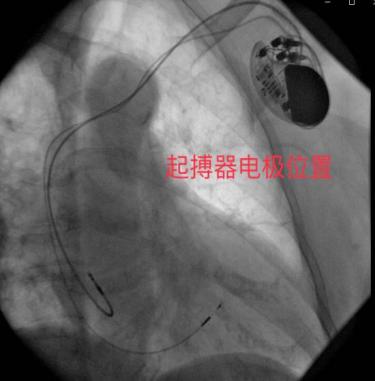

但希氏束电极与常规双腔电极差异较大,定位及固定比较困难,手术难度较高,需要起搏与电生理技术的结合,对术者的解剖定位认识及技术要求更高。经过充分的术前准备,巩贵宏团队经静脉途径,将导线从右室间隔面深拧穿间隔至左室间隔面内膜下的左束支区域,起搏夺获左束支主干或左前、左后分支近端,达到跨越阻滞部位,保持左室电同步。患者手术顺利,术后患者恢复良好,起搏器工作正常。